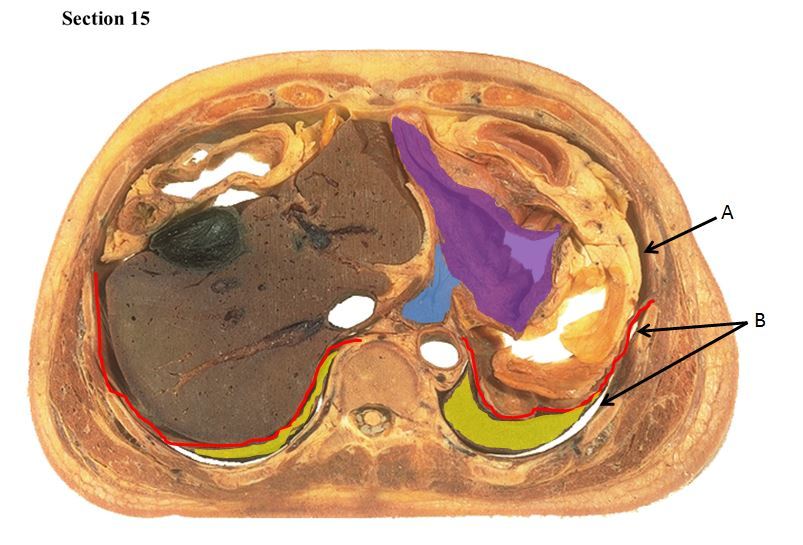

15

Q

The red muscle is the _____

The orange organ is the _____

A

diaphragm

liver

16

The blue organ is the _____ and the yellow organ is the _____.

The purple structure is the _____

right lung

left lung

esophagus

17

The red line is a muscle called the ___ which separates cavity A called the ___ from cavity B which is called the ___

peritoneal cavity

pleural cavity

18

In cavity A, the blue organ is the ___ and it deposits materials into the purple organ which is the ___

stomach